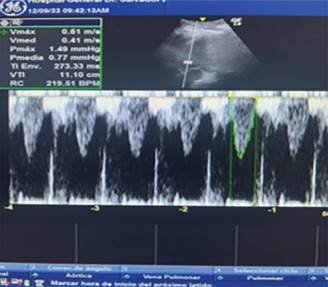

Durante su evolución, se evidencia deterioro hemodinámico con aumento de requerimiento de vasopresores con disminución de SvO2, en la ecocardioscopia se observa hipocinesia del ventrículo izquierdo con una integral velocidad tiempo de 11.1 cm/s, y diámetro de tracto de salida del ventrículo izquierdo de 1.65 cm, con gasto cardiaco de 2.38 L/min (Figura 1 y 2) como deterioro del estado ácido-base con presencia de acidosis metabólica de anión gap elevado (Tabla 3) concomitante con acidosis metabólica de anión gap normal.

Figura 2: Ecocardioscopia. Hipocinesia anterior con dilatación de ventrículo izquierdo con integral velocidad tiempo de 11.1 cm/seg.